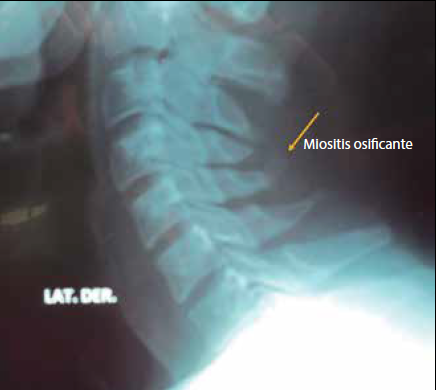

Los estudios anatomopatológicos muestran una masa de fibroblastos inmaduros en el centro y, en la periferia, islotes de tejido osteoide desorganizado3. Se muestran 3 casos de MOC: mujer de 43 años cuyo trabajo desde hace 20 años consistía en cargar rollos de tela (figura 1); varón de 46 años que desde hace 25 años laboraba como estibador en una bodega (figura 2); masculino de 26 años, con 10 años de trabajo en fontanería (figura 3). Estos pacientes realizan movimientos repetitivos contra carga repetitiva durante 8 horas de trabajo por 5 días de la semana, por lo que se origina una lesión muscular por sobreuso; su sintomatología es: dolor moderado y sensación de rigidez de cuello principalmente al momento de levantarse, que cede espontáneamente con movimiento de calentamiento muscular; se encuentra en la exploración a estos pacientes, músculos paravertebrales cervicales, trapecios, esplenios y angular del omoplato con sensación de tirantez, se palpan en todos los casos, masas alargadas por arriba de apófisis espinosa de C7 localizadas en la línea media, limitando la flexión de columna cervical por rigidez muscular; se anota que son casos crónicos, el tratamiento implica: a) modificación de las actividades laborales, b) termoterapia con aplicación de compresas, c) ejercicios de estiramiento moderado en flexión de músculos de nuca, d) analgésicos simples como paracetamol en caso de dolor y relajantes musculares de uso nocturno en caso necesario. La evolución de los pacientes después de 60 días de tratamiento fue satisfactoria por disminución de la sensación de rigidez cervical, aumento de los grados de flexión cervical y desaparición de dolor matutino. Se anota que se logró cambio de puesto laboral gracias a reporte médico. Debe efectuarse diagnóstico diferencial con la miositis (fibrodisplasia) osificante progresiva4 o enfermedad de Münchmever, padecimiento raro de origen desconocido, que se presenta en niños, adolescentes o adultos jóvenes y produce una difusa calcificación ectópica y osificación en fascias, aponeurosis y otras estructuras fibrosas relacionadas con el músculo.